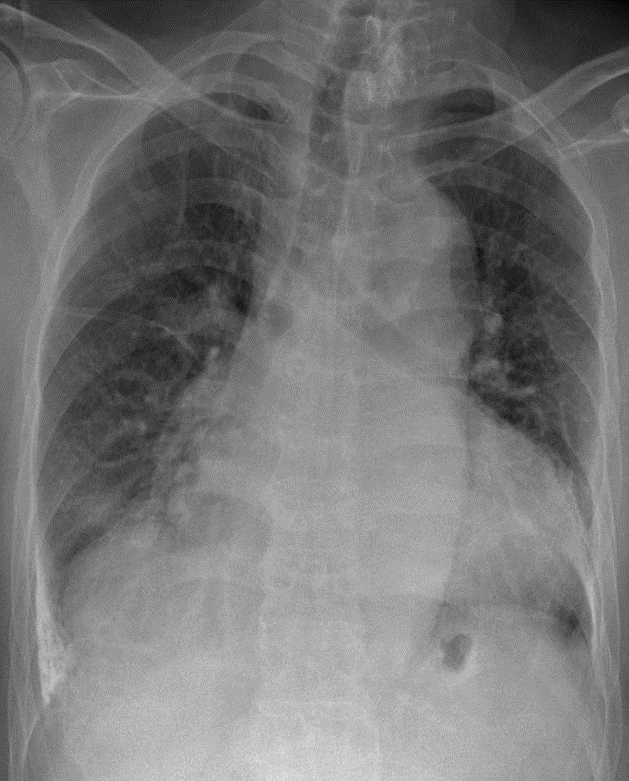

1- Cung động mạch chủ dãn 2-Tim (T) lớn 2-Đóng vôi màng phổi phải